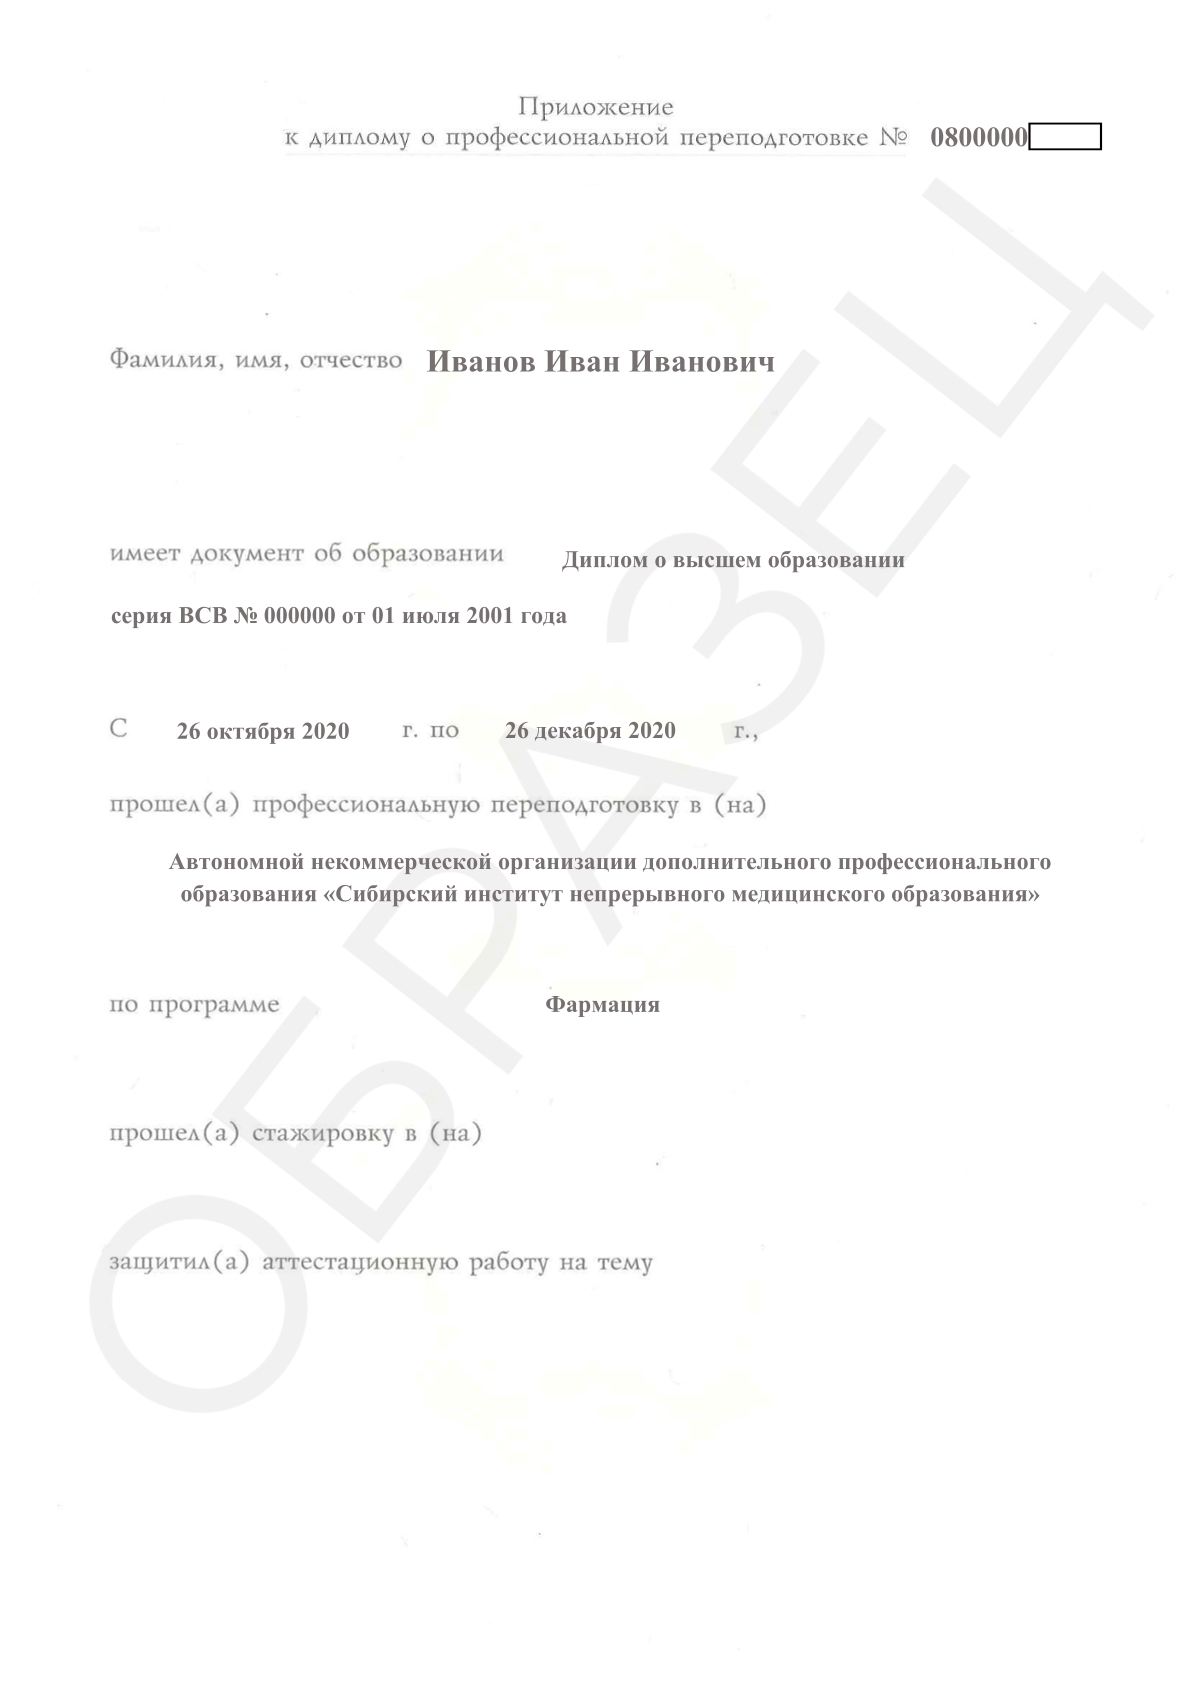

Смотреть документ

Смотреть документ